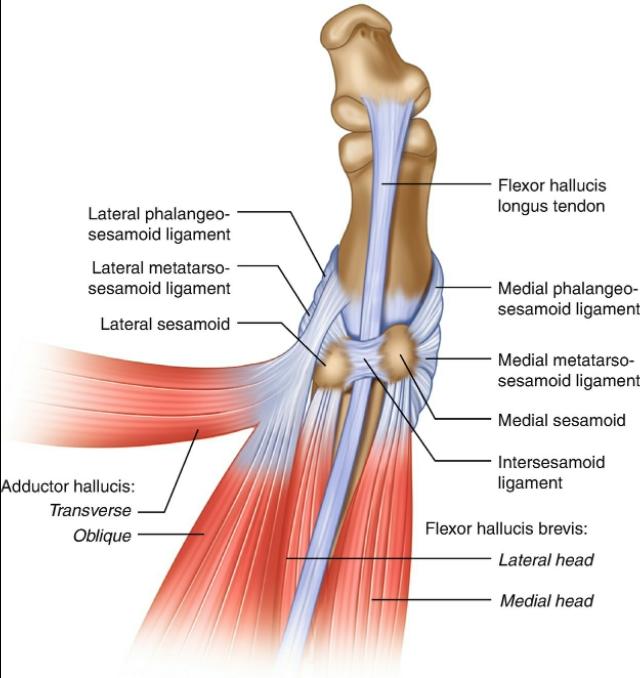

拇趾或第一趾,在脚的中远部。它由第一跖骨(有两个籽骨的关节)、第一近节指骨和第一远节指骨组成。所以拇趾不像其他脚趾有一块额外的骨头叫做中间趾骨。

第一个脚趾有三个滑膜关节。第一个关节是跖跗关节位于内侧楔形骨和第一跖骨之间,不允许大幅运动。第二个关节是跖趾关节,连接第一跖骨和第一近端趾骨。该关节允许第一个脚趾的弯曲和伸展,以及向第二个脚趾中心的小幅度的外展和内收。它同时被韧带加强(包括:跖趾侧副韧带和跖板)。最后一个关节是趾间,是第一趾两趾骨之间的连接。这个关节只允许屈曲和伸展,它也被韧带加强。

如前所述,有两块籽骨与第一块跖骨相连。这些籽骨保护附着在肌肉上的肌腱,但它们的主要功能是通过伸展杠杆帮助肌肉产生更多的力量。

其他结构:胫前肌、拇长伸肌、腓骨长伸肌、拇长屈肌、拇短伸肌、拇外展肌、拇短屈肌、拇内收肌、背内侧肌、跖腱膜。

这种拇外翻形成的机制始于拇展肌的过度拉伸(例如,穿着过紧鞋)。第一近节趾骨的基部开始侧化和外展。在步态中,前脚变成旋前,伸展内侧副韧带和第一个MTP关节的囊膜结构。由于第一MTP关节由多个骨骼、韧带、籽骨组成,并且附近有肌肉,所以该结构在运动或伸展时会影响其他结构。这样,一旦达到拇趾外翻的临界程度,第一跖骨开始进入内翻位置。这样,拇趾就被推到外翻的位置。关节囊变弱,拇展肌腱变成拇跖屈肌。当情况变得更糟时,多块肌肉的牵拉轴被侧向化,往往会使情况恶化。